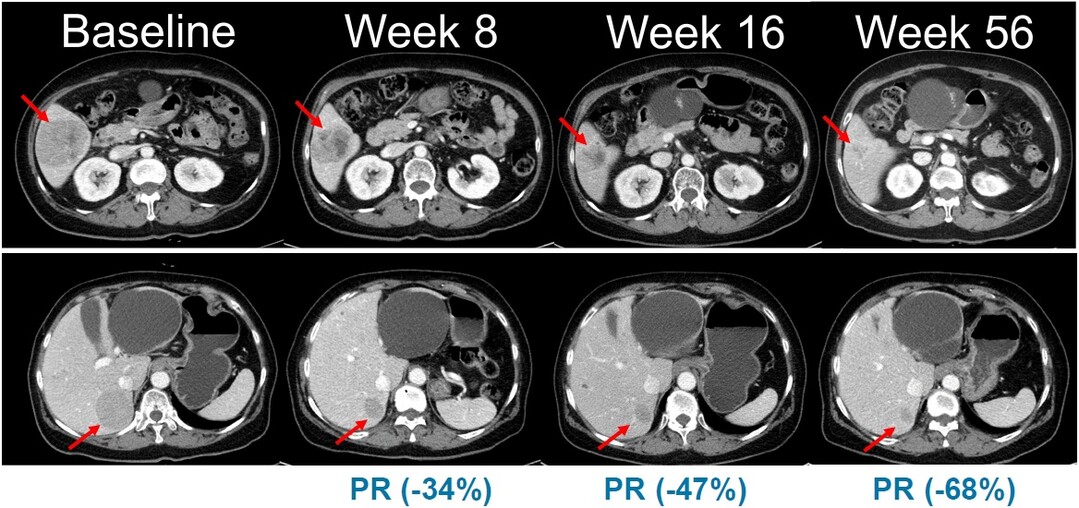

| NRAS 돌연변이 흑색종 환자를 대상으로 진행된 벨바라페닙과 코비메티닙 병용요법 임상시험에서 시간 경과에 따른 병변 변화가 관찰된 복부 CT 영상 [사진=한미약품] |

이번 임상 2상은 총 45명의 환자를 대상으로 표적 항암신약 벨바라페닙과 MEK 억제제인 코비메티닙(Cobimetinib) 병용요법의 유효성과 안전성을 평가하기 위한 다기관, 단일군 시험으로 진행된다.